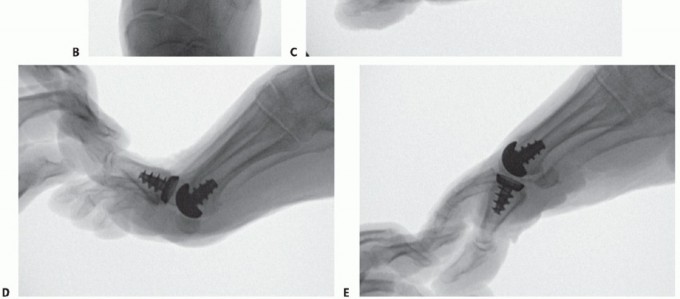

Given the lack of significant rates of loosening seen with this implant, recent FDA approval has been obtained for a novel total toe arthroplasty design (Arthrosurface ToeMotion Total Toe Arthroplasty) using the same tapered screw fixation method within proximal phalanx (FIG 9). A proximal phalangeal component with polyethylene insert was created as a complement to the metatarsal HemiCAP DF implant in an effort to address progressive arthritic changes of the proximal phalangeal articular surface. When significant involvement of both sides of the joint are seen at the time of the index procedure, use of the ToeMotion total toe arthroplasty design would be more appropriate than a hemiarthroplasty alone with the desired goal of providing a more predictable procedure for pain relief.

FIG 9 • (continued) B-E. Radiographs of ToeMotion total toe arthroplasty.

FIG 11 • A. HemiCAP conversion to ToeMotion total toe arthroplasty. HemiCAP DF must be used on metatarsal side to match phalangeal component with polyethylene insert. Centralized pin is placed within proximal phalanx.

* B. Phalangeal reamer is used for inlay phalangeal component. C,D. Following tapping, taper screw-based phalangeal tray component is placed. (continued)

FIG 11 • (continued) E,F. Following assessment with modular trials, polyethylene insert chosen and placed with delivery device which locks into phalangeal tray. G. Final components for ToeMotion implant.